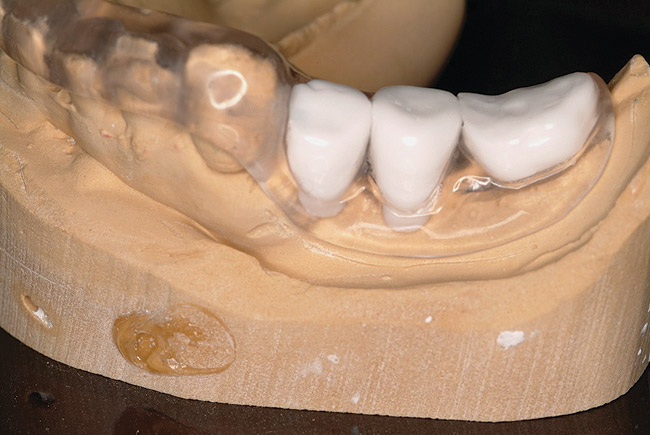

Figure 9: Stereolithic model of edentulous maxilla and bone-supported guided surgery stent.

Figure 9